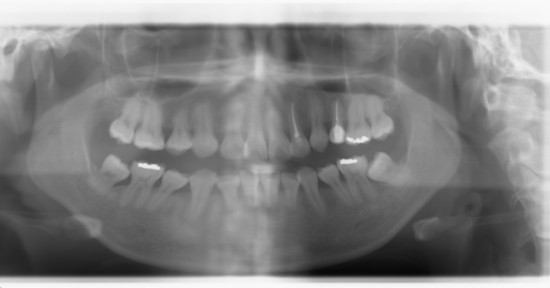

안녕하세요 선생님 중학생때 치과기술이 그닥 좋지 않은 외국에서 교정을 했는데 제대로 교정이 되지 않았어요. 사랑니 이런걸 감안하지도 않고 끝나고 엑스레이도 찍어보지 않더군요. 어처구니가 없긴하지만 그땐 말...